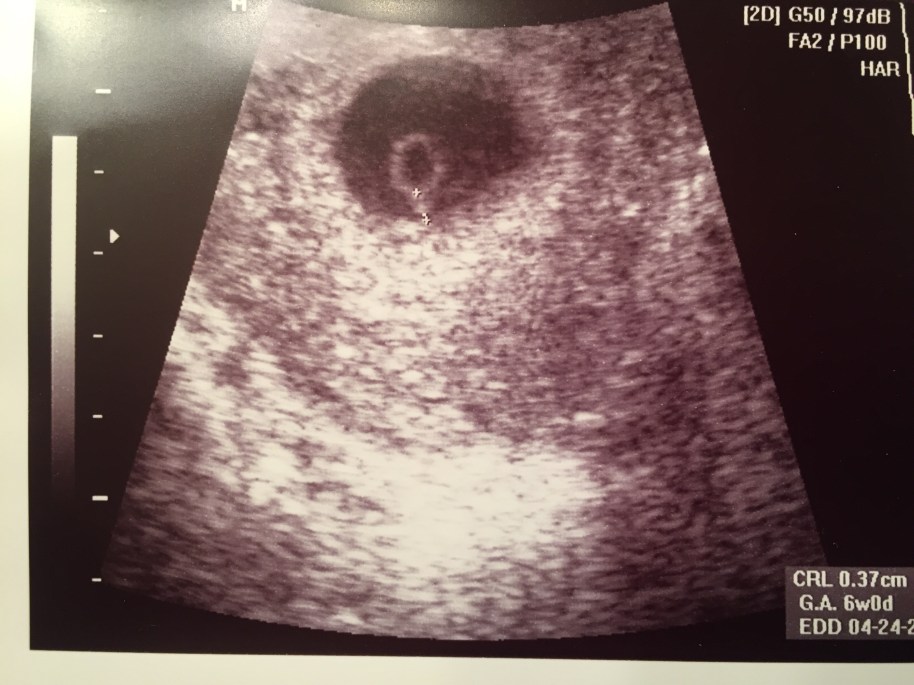

Then we had our doctor’s appointment and sonogram to confirm the pregnancy. The sonographer was really excited, told us that at 9 weeks the baby would look great, that it was an exciting week to see it. So we were eagerly optimistic to see our baby. Once she found the baby with her sono wand, we could hear a very faint heartbeat and see a blob of a gummy bear on the screen. It was our baby! Since this was our first experience with a sonogram, we didn’t know what we were really seeing. She said it looked fine, with a small but good heartbeat, and that it was measuring around 6 weeks. Woah woah, hold the phone. 6 weeks? I knew that couldn’t be right. It should be 9 weeks. I felt like something was wrong with her machine, not with the baby. We met with our OB and she said I must have had our dates mixed up and to come back in a week to make sure it was growing. My husband and I were cautious but still optimistic. We went back in a week for another sonogram and the baby was measuring just slightly bigger but there was no heartbeat. I was 10 weeks pregnant with a baby that stopped growing almost 4 weeks ago. I was shocked, upset and confused. My OB said we would schedule a D&C surgery later that week. And that was the end of our first pregnancy.